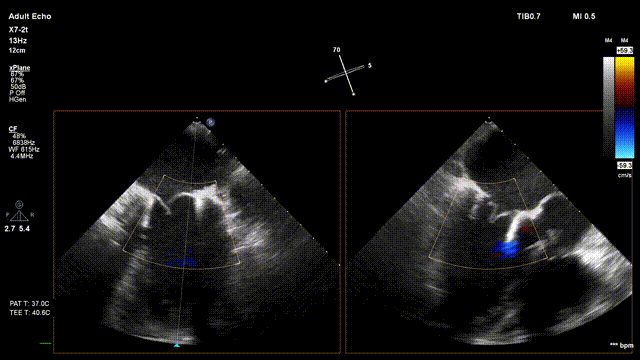

术前超声评估:

术前TTE超声提示二尖瓣大量反流

术后超声评估:

术后无反流、左室流出道通畅